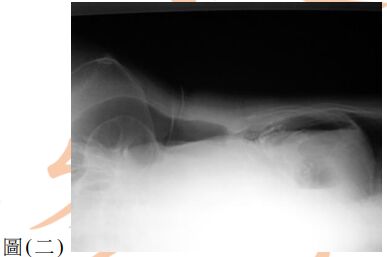

13. 80歲女性為長期糖尿病、高血壓及中風不良於行之病人,因急性腹痛來急診就醫,其平躺之腹部X光如圖(一),另一張左側躺之腹部X光檢查如圖(二),下列敘述何者正確?(A) 推測有腹腔積水,可能為腹腔腫瘤導致 (B) 推測有腹部脹氣,可能為腸阻塞導致 (C) 推測有腹腔積氣,可能為腹腔內中空臟器破裂導致 (D) 為正常腹部影像,只須持續追蹤